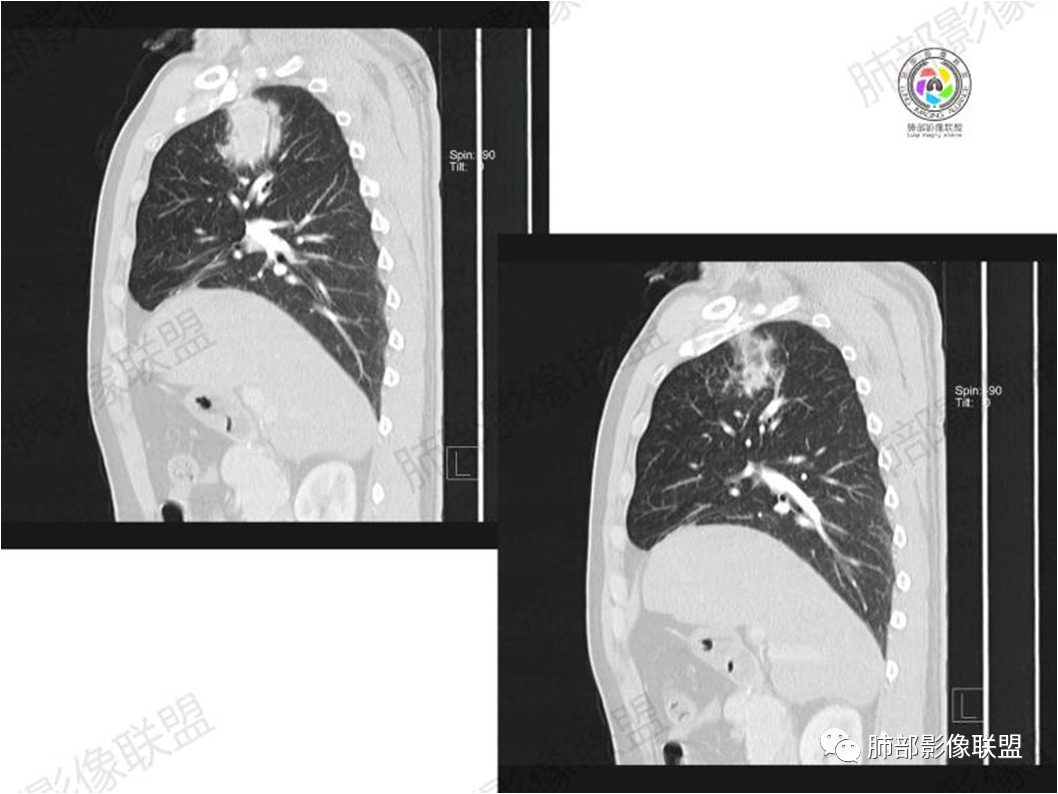

胸部CT:

中年男性,偶有咳嗽,右肺上叶近纵膈旁占位,内可见僵硬的支气管和小空泡征,病灶边缘可见分叶,毛刺,增强病灶中度以上不均匀强化,可见血管造影征,考虑恶性病变,腺癌可能性大。

中年男性,右肺上叶尖段团片病灶,密度均匀,内部支气管充气相,渐进狭窄,强化均匀,血管造影,纵隔侧未见侵犯,诊断:良性,慢性非特异性炎症/机化性炎症,IMT

右肺上叶纵隔胸膜侧一实性肿块,与纵隔胸膜宽基底相连,局部脂肪间隙消失,形态欠规则,内部可见多个小空泡,平扫密度尚均匀,增强后可见点条状强化,内部穿行血管,周围肺组织干净,纵隔淋巴结略肿大,男性44岁,只有咳嗽,考虑恶性肿瘤,腺癌,鳞癌。鉴别结核,OP,炎性假瘤。

右肺上叶近纵膈旁肿块,密度均匀,边缘分叶,毛刺,气管受压变窄,不均匀强化,可见血管造影征,考虑淋巴瘤,鉴别炎性假瘤。

中年男性,右肺上叶纵隔旁软组织肿块,边缘膨隆、毛糙,可见多发分叶,支气管穿行,部分截断,增强后密度欠均匀,纵隔内见多发小淋巴结,首先考虑恶性,腺癌,鉴别淋巴瘤

中年男性,右肺上叶纵隔旁肿瘤,稍膨隆,有毛刺,支气管穿行,远端闭塞,强化均匀,血管走行尚可,考虑淋巴瘤可能性大(支气管远端闭塞,不太符合),鉴别腺癌(气管穿行后闭塞,不太符合),op(病灶稍膨隆)

患者中年男性,咳嗽就诊,无其他不适。胸部CT:右肺上叶尖段上纵膈旁肿块,边界清楚,边缘光滑,内见支气管受压变窄,伴阻塞性改变,增强均匀强化,见血管造影征。综合考虑恶性病变,小细胞肺癌或淋巴瘤。气管镜活检应能明确。

中年男性,右肺上叶纵隔旁实性病灶,边缘有彭隆,有平直,有分叶,有尖角,病灶边缘中心可见支气管征,周围少许磨玻璃,边缘模糊,增强后动脉期病灶可见强化血管影,渐进性强化,临近血管界限清晰。考虑炎性病灶,普通炎性肉芽肿?结核?炎性肌纤维母细胞瘤?鉴别腺癌,淋巴瘤